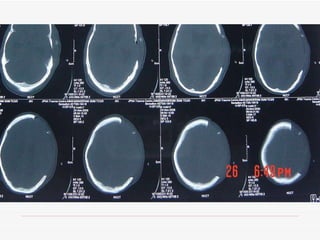

Decompressive craniectomy is used at JPNATC to treat severe traumatic brain injuries. Between January 2008 and November 2008, 24.1% of patients with severe head injuries underwent decompressive craniectomy. The indications for decompressive craniectomy at JPNATC include severe head injury with acute subdural hematoma, midline shift, and mass effect; intracerebral contusions with mass effect and midline shift; and diffuse axonal injury with effaced cisterns and intracranial pressure above 20 despite maximum medical therapy.